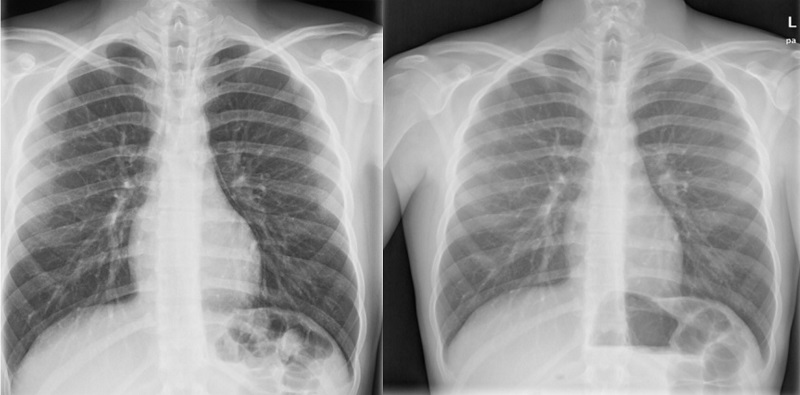

The patient was admitted for evaluation and treatment. She underwent serial endoscopic balloon oesophageal-pyloric dilations, developing pneumomediastinum with mild mediastinitis as a complication of one of these procedures. The diagnosis was made by chest radiograph, which was indicated on account of onset of fever 24 hours after performance of an upper endoscopy (Figure 4). The illness resolved with intravenous antibiotherapy, and the patient did not require respiratory support, haemodynamic support or drainage. The follow-up evaluations were normal, and there was no recurrence.

| Figure 4. Case 6. Female adolescent aged 15 years that presented to the emergency department with severe epigastric pain of 24 hours’ duration associated with nausea without vomiting, diarrhoea or fever. The diagnosis was made by chest radiograph, which was indicated on account of onset of fever 24 hours after performance of an upper endoscopy |

![]() |

The pneumomediastinum resolved completely within 5 days, but the patient remained hospitalised for 45 days for management of the underlying disease.